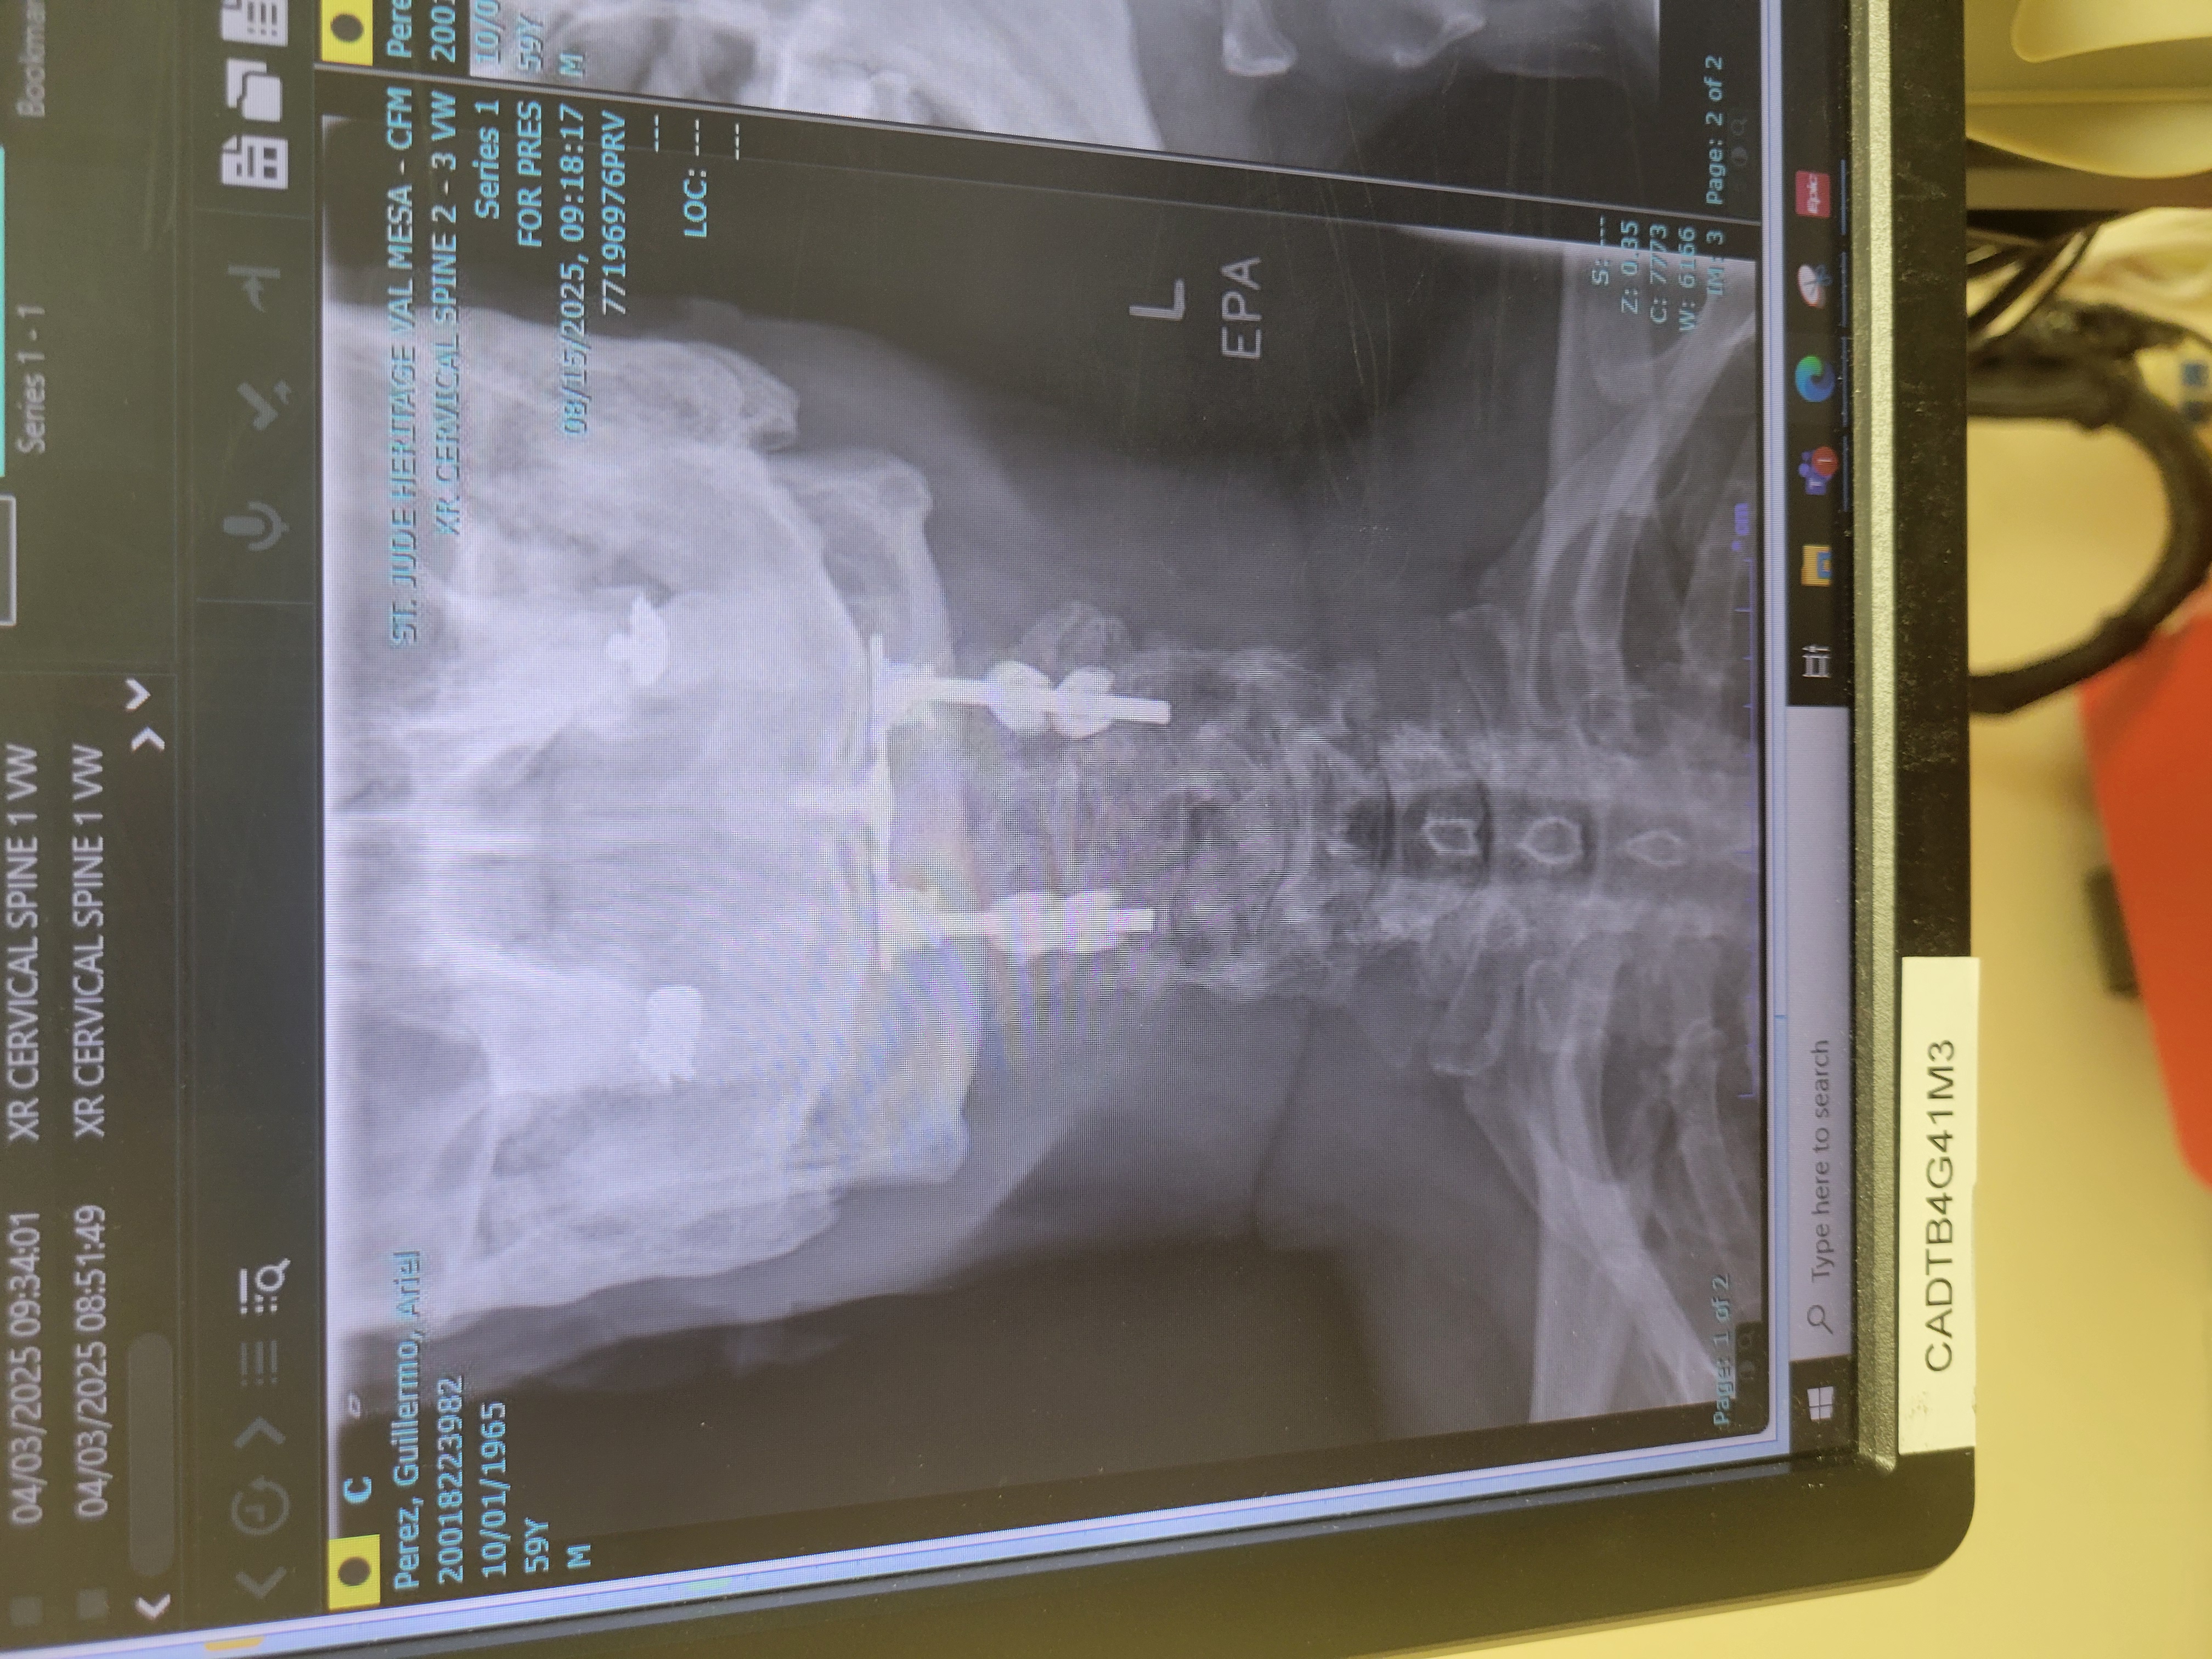

Great doctor, i broke my C1 after 4 months wearing a brace my c1 was worse, I spoke with him and I was ready for surgery he explain all the thing the can go wrong , I had surgery a moth after our meeting , Great hospital, great staff its been 8 moths and I feel great i was back in the gym 6 weeks after surgery.